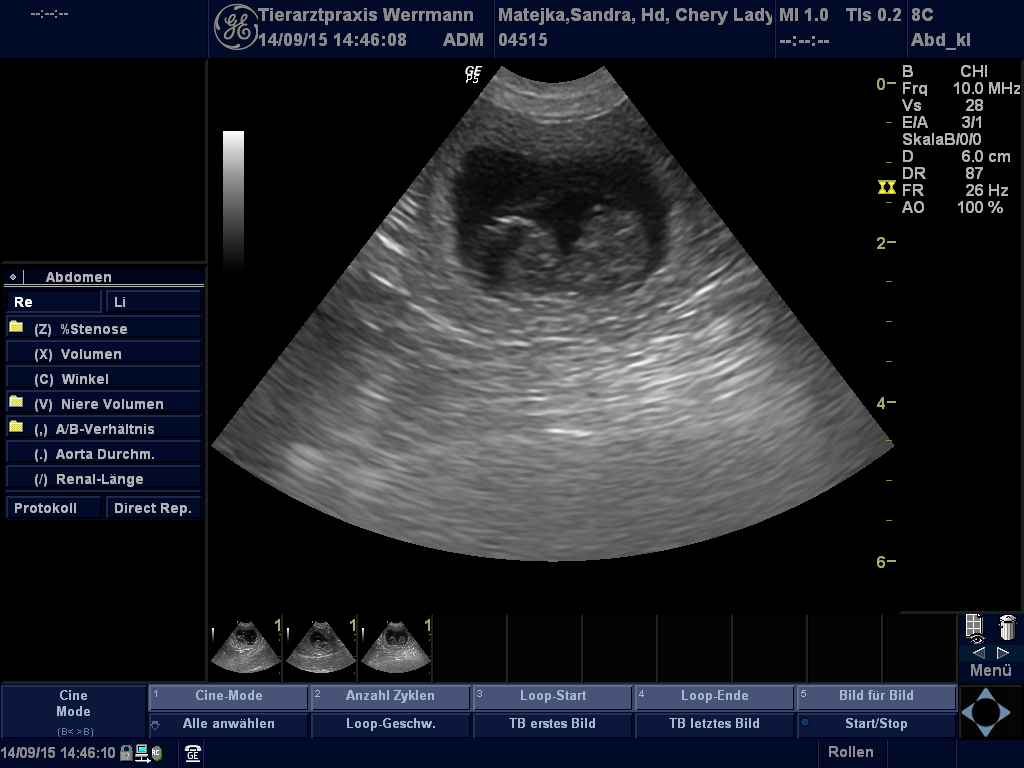

Ultraschallbilder